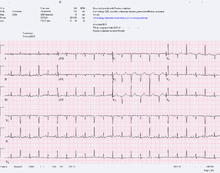

- An ECG showing electrical alternans in a person with a pericardial effusion.